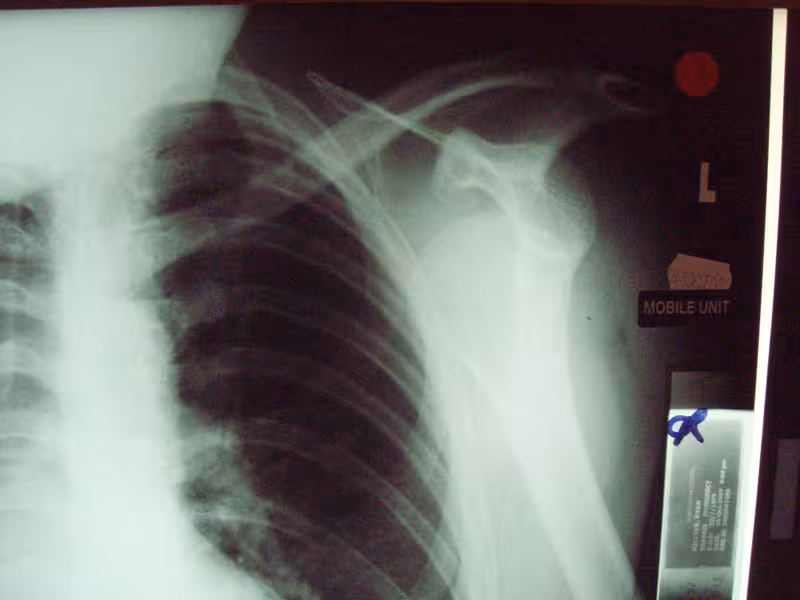

I’m having a Bankart repair done on my shoulder on Monday. Below are some photos of my shoulder. Uunfortunately you can’t see much damage as it’s the soft tissue which needs repaired. My shoulder pops out of the socket on a regular basis ever since I was body checked in a non-contact ice hockey game. I even managed to dislocate it picking up a bottle of coke the other day!